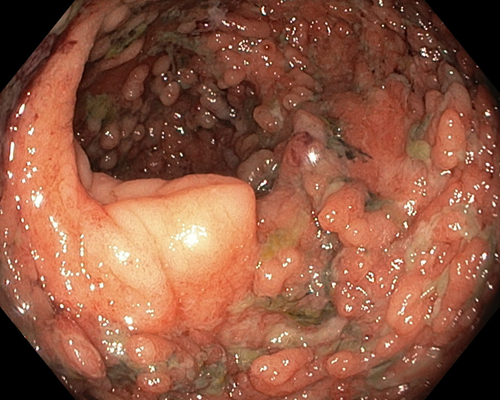

肛門癌圖片

肛癌早期症狀